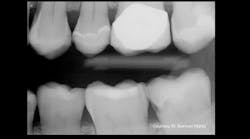

Due to contact with neighboring teeth, identification of interproximal caries is typically performed using radiographs. Identification of incipient enamel lesions can be aided with artificial intelligence (AI) tools (OverJet AI, Pearl), which have been shown to improve sensitivity for identification from 64% without AI to 75% with AI.7 Interproximal caries can also be identified with near-infrared transillumination (DIAGNOcam, KaVo; VistaCam, Durr Dental), which demonstrates caries as dark areas in which higher porosity carious enamel absorbs more light.

Prior to enamel cavitation, incipient enamel lesions should be treated with nonoperative techniques with the goals of arresting the caries process, remineralizing the lesion, and preventing the cavitation of the outer wall of enamel. Cavitation is assessed visually for smooth surface and occlusal caries lesions. Cavitation is deduced from radiographic extent for interproximal lesions. Studies have indicated that only 11%–15% of radiographic lesions confined to enamel are cavitated.8,9